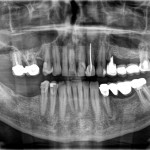

CASI CLINICI: